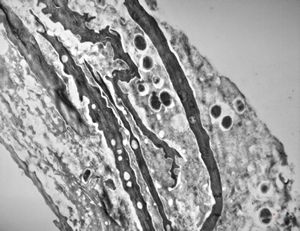

M,68y. | auditory meatus … otitis externa mycotica

M,68y. | auditory meatus … otitis externa mycotica - (toluidine-blue- stained semithin section)